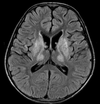

Deterioration of conscious level and agitation. Patient had gastric surgery 2 months ago for peptic ulcer.

What is the diagnosis?

Abnormal signal bilateral and symmetrical involving the medial and posterior aspect of both thalami displaying bright signal in DWI, T2 and FLAIR.

Diagnosis: Wernicke Encephalopathy.

Case Discussion

Previous gastric sugery or Bariatric sugeries are predisposing factors to various deficiency syndromes. Thiamine deficiency causes acute encephalopathy usually affects the medial thalamus, tectal plate and periacqueductal grey matter.